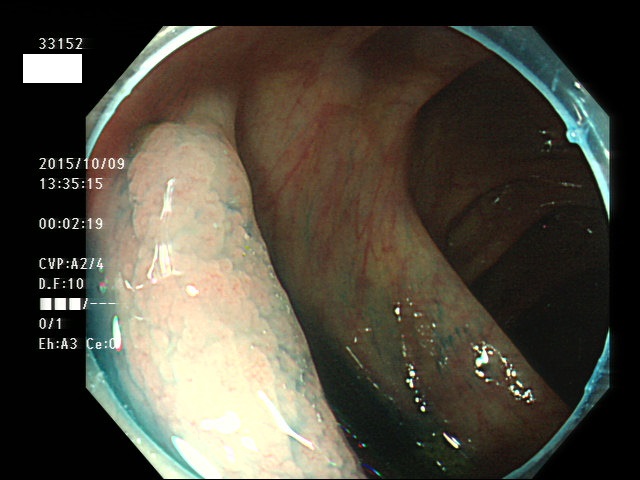

上記100名より抽出した平坦・陥凹型腺腫(=癌化の危険が高いが見落としやすい病変)の内視鏡写真